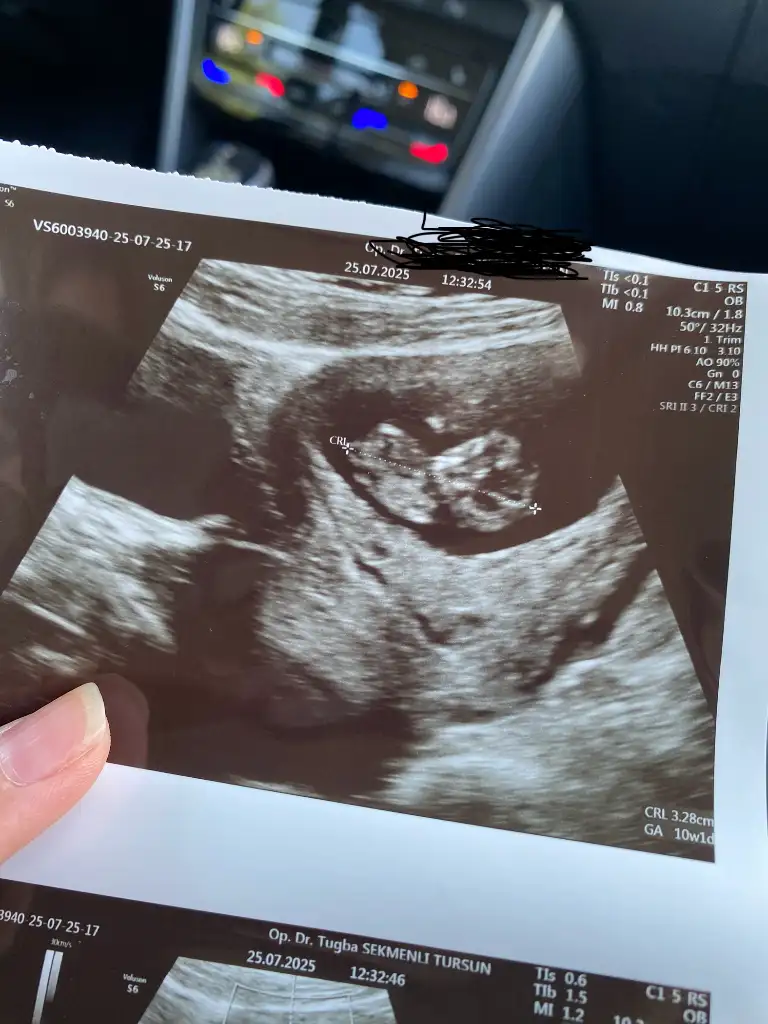

Kızlar bugün doktor kontrolümüz vardı bir hafta sonraya randevu verdi ense kalınlığı ve cinsiyet tahmini için sizce erken değil mi ya da cinsiyet tahmini yapabilecek olan var mı 10+2 :KK68:

teşekkür ederim😇 bir kızım var. sağlıklı ve hayırlı evlat olsun da cinsiyet önemli değil.

doktor da kese ortada. Çok güzel bir konum bu demişti. Bakalım.

Benimkide tam ortadaydı. 10. haftada ultrasonda sola kaymış. ☺️ O yüzden bizimkilerin cinsiyet tahmini tam ortada🌸 İnşallah gönlünüzdeki olur ama. 12. haftada belli olur❤️

Ben bir şey soracağım. Şu uç kısmında 3 uzantı varya. Onlar tam olarak ne :) Doktor bana bacak diye gösterdi ama burda cinsiyet için tahmin ediyorlar🤣 10. haftada bellı olmuyormuş açı. Kız erkek aynı diye okudum ama bilemiyorum😌

Ahh cinsiyet tahminim hiç yok;) ama benim 13. Haftanın sonuna detaylı ultrason verdi doktorum tüm boyutlarına ense burun vs bakıcak cinsiyeti de görebileceğini söyledi